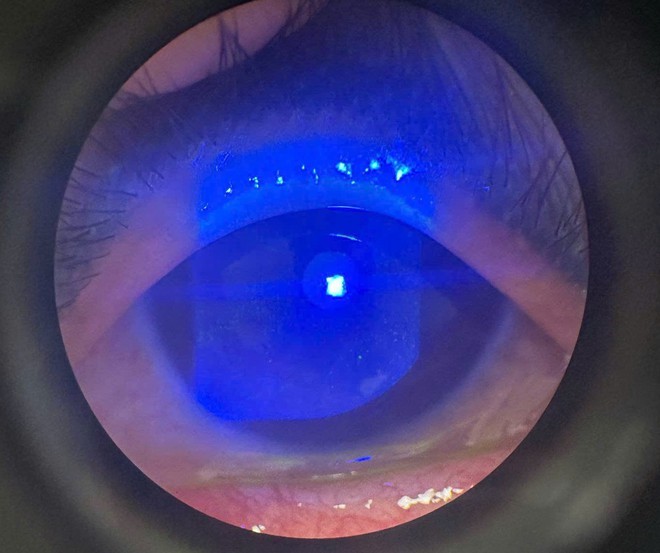

Suýt mù vì tự chữa mắt tại nhà, bác sĩ cảnh báo thói quen nhiều người dễ mắc

Thứ Ba, ngày 13/05/2025 02:54Người bệnh N.T.T, 49 tuổỉ, đến TTYT huyện Thanh Sơn, Phú Thọ trong tình trạng mắt phải sưng nề, đỏ rát, đau nhức dữ dội và chảy nhiều dịch nhầy trong. Theo lời kể của người bệnh, do thấy...